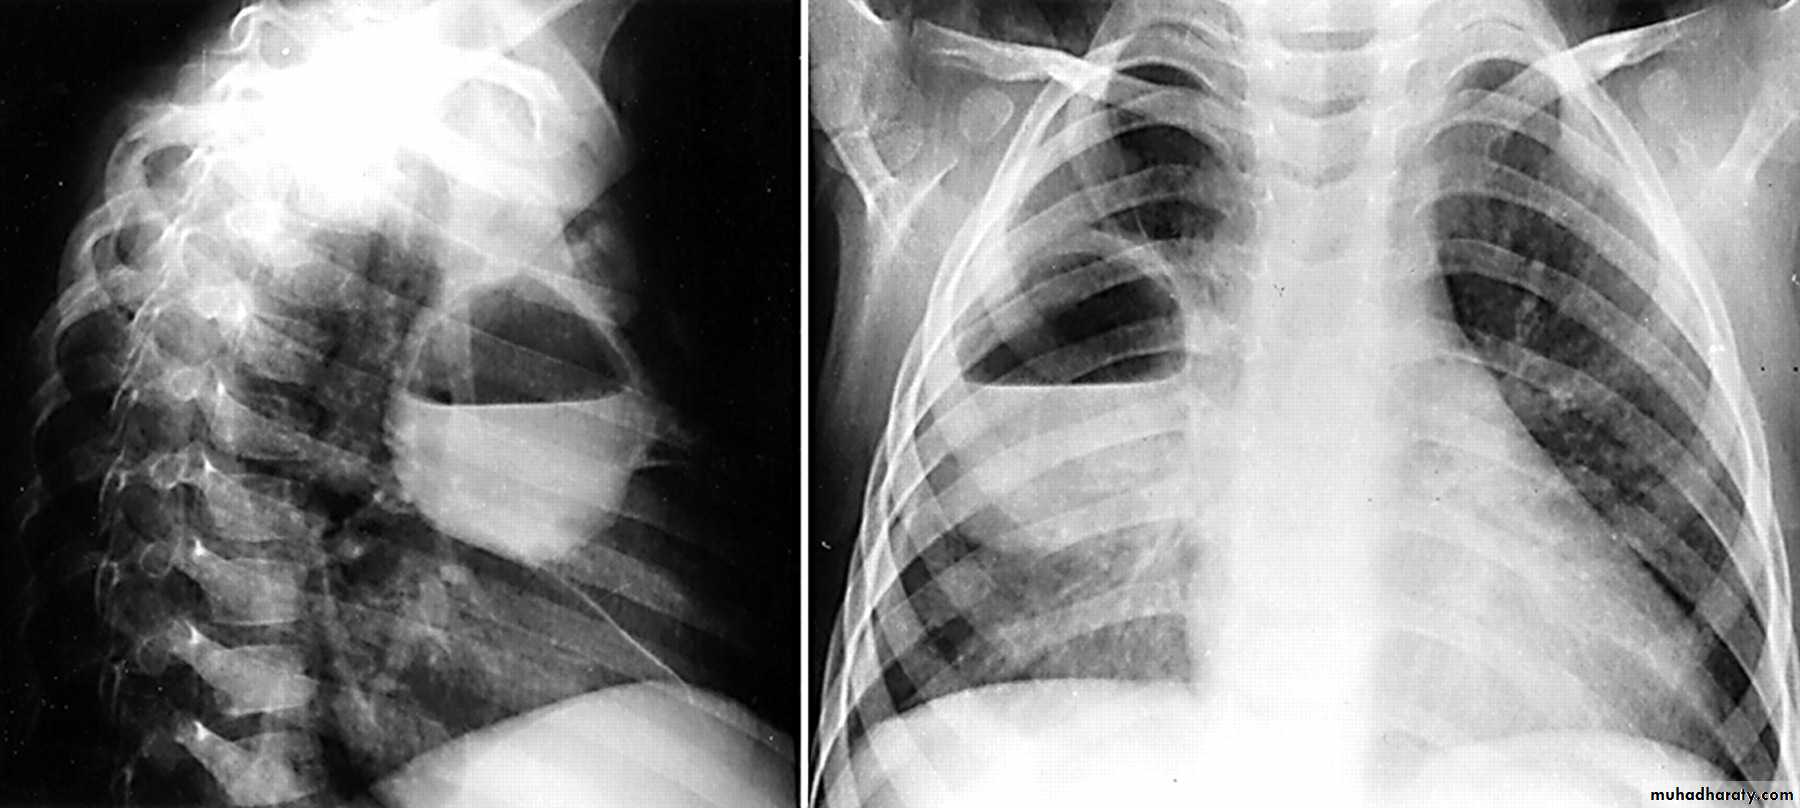

A Pancoast tumour, otherwise known as superior sulcus tumour, refers to a relatively uncommon situation where a primary bronchogenic carcinoma arises in the lung apex and invades the surrounding soft tissues , adeno CA being the most frequent type ,Plain film

Plain films demonstrate a soft tissue opacity at the apex of the lung. Occasionally with rib involvement with extension into the supraclavicular fossa may be evident with surrounded bony destruction . Lordotic views may be helpful .

Pancost tumor